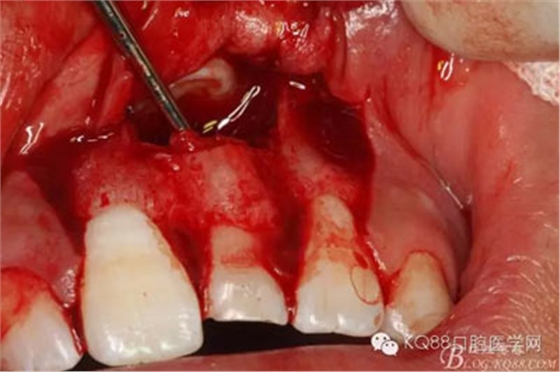

圖5.局部無痛麻醉下。行唇側(cè)齦溝內(nèi)切口

圖6.雙側(cè)垂直附加切口,形成梯形瓣

圖7.翻瓣、注意是全厚瓣。

圖8.翻開牙齦粘膜瓣,可見左乳Ⅰ根方骨面隆起